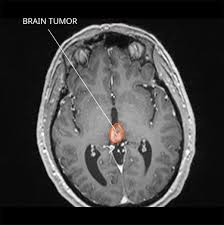

To help you prepare, here's a look at what to expect. Hello, thank you for using healthcaremagic to post your health query. Ct scan can see very well if a cancer has spread. A ct scan can help doctors find cancer and show things like a tumor's shape and size. The doctor ordered a ct scan and at some point, she commented that it would be good news if the scan did not show an obstruction, as this could possibly be a malignant mass—having originated as colon cancer but having infiltrated outside of the colon where a ct scan would pick it up. There are few features that can help distinguish on ct scan. They show the different appearances of acc lung mets. A ct scan can detect potential cancer in a lung. They may also use it to learn more about the cancer after they find it. An arm or chest radiograph looks all the way through a body without being able to tell how deep anything is. Acc has a tendency to spread to the lungs among other organs. According to hopkinsmedicine.org, a ct scan can be helpful in diagnosing some types of brain tumors, particularly those near or involving bone. the cat scan can also show bleeding, swelling, bone and tissue calcification that would be caused by a cancer. (turned out my father had diverticulitis.)

A ct scan can help doctors find cancer and show things like a tumor's shape and size. Benefits of a colon ct scan over other investigative methods include its ease of use and the fact that sedation is not necessary. Also, clinical presentation also can help in the decision making proces. The scan lets them:learn the cancer's stage. The mass also invades the anterior abdominal wall. Ct scans are most often an outpatient procedure. Hello, thank you for using healthcaremagic to post your health query. You may need to have a ct with contrast. What does cancer look like on ct scan. One primary neck cancer that might be seen on a neck scan is thyroid cancer. The computer puts them together to make a 3 dimensional (3d) image. What is a lung ct scan and how does it work? Abdominal scans can be used to help a doctor pinpoint the location of a tumor before a biopsy is.